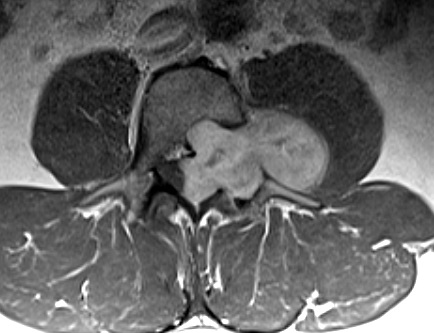

Craneal es izquierda; medial es inferior.

En esta imagen, medial es superior